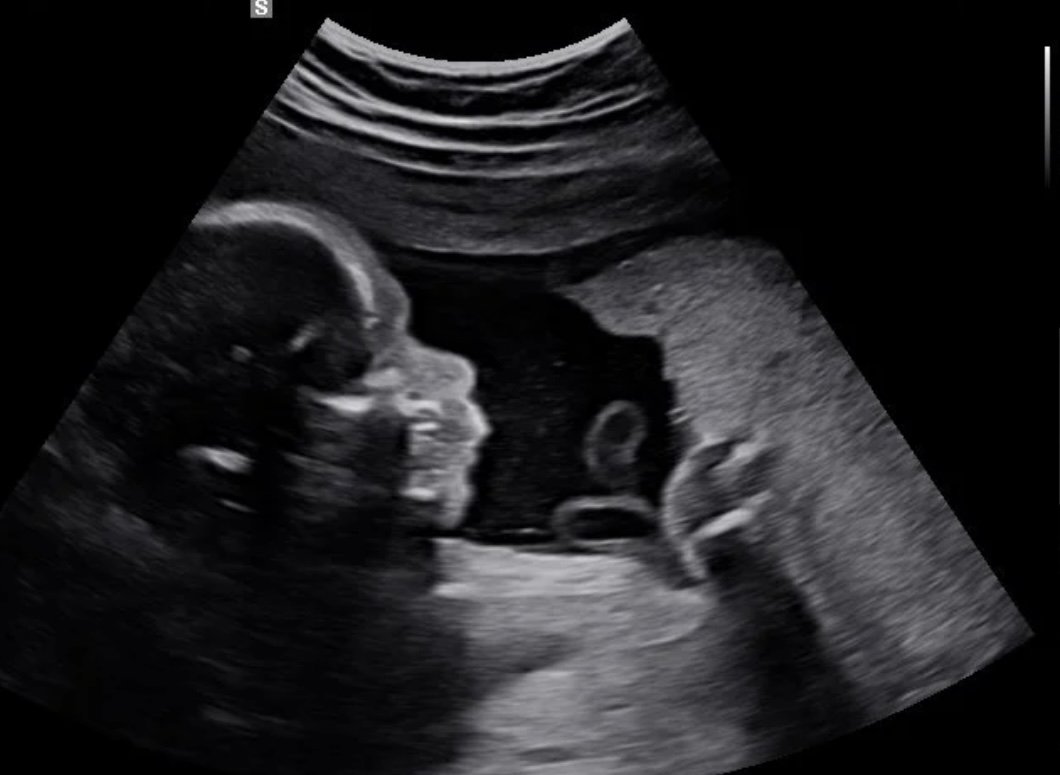

See your baby in 2D, 3D, and 4D. Experience the joy of meeting your baby before birth. Our elective ultrasounds are designed to create unforgettable moments for families. Enjoy our cozy environment of peace in an ultrasound in Tampa or Central Florida.

Our elective 4D sessions capture your baby’s real movements and transform them into breathtaking 8K baby portraits, memories you can keep forever.